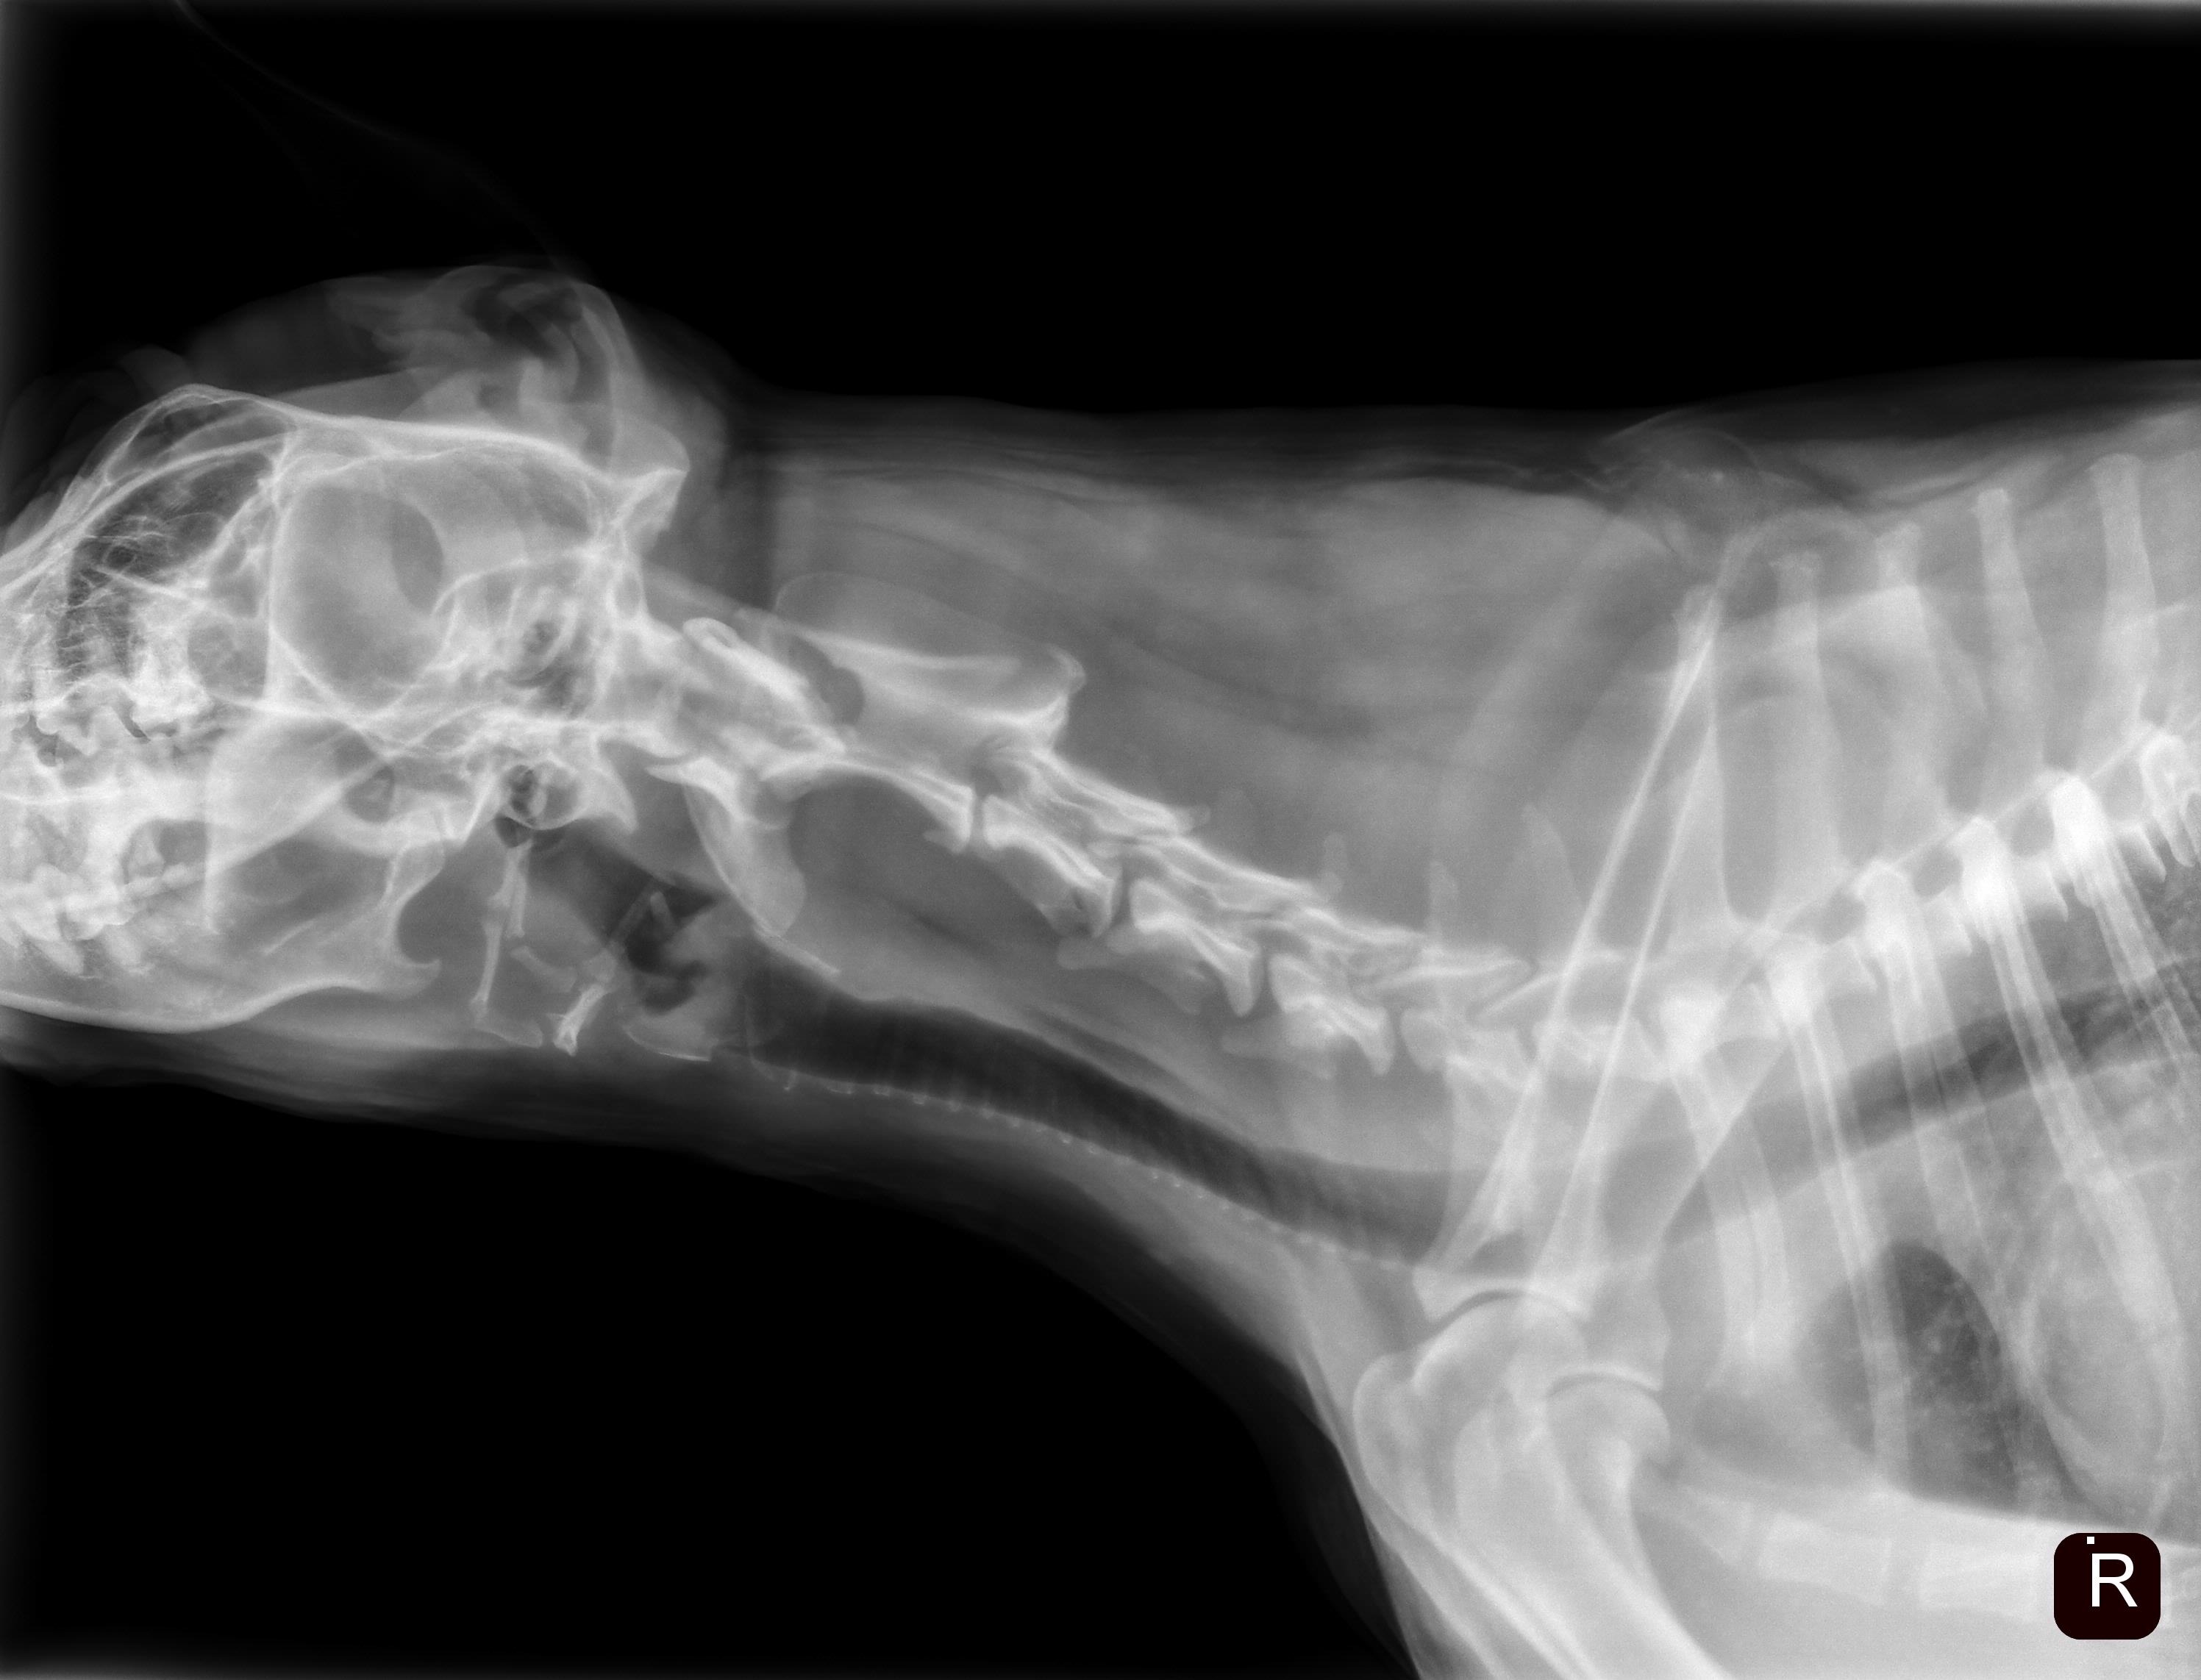

We rushed Sadie to the vet where they determined she had obvious brain trauma and swelling. X-rays revealed a C1 and C2 fracture.